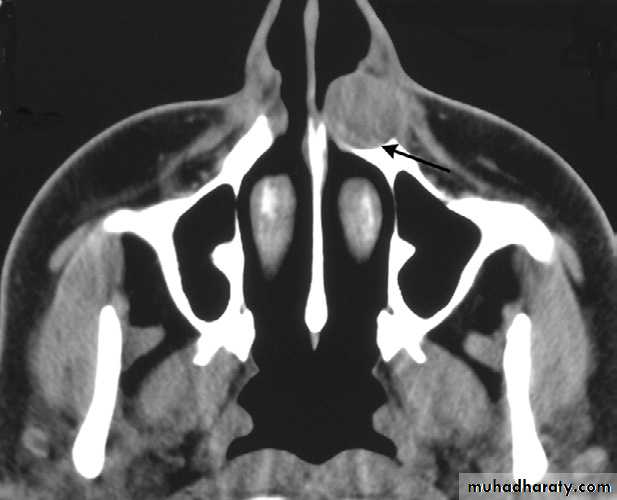

Nasolabial Cyst

The exact origin of nasolabial cysts is unknown. They may be fissural cysts arising from the epithelial rests in fusion lines of the globular, lateral nasal, and maxillary processes. Alternatively, the source of the epithelium may be from the embryonic nasolacrimal duct.Location. Nasolabial cysts are primarily soft tissue lesions located adjacent to the alveolar process above the apices of the incisors. Because this is a soft tissue lesion, plain radiographs may not show any detectable changes. The investigation could include either CT imaging or magnetic resonance imaging, both of which can provide an image of soft tissues